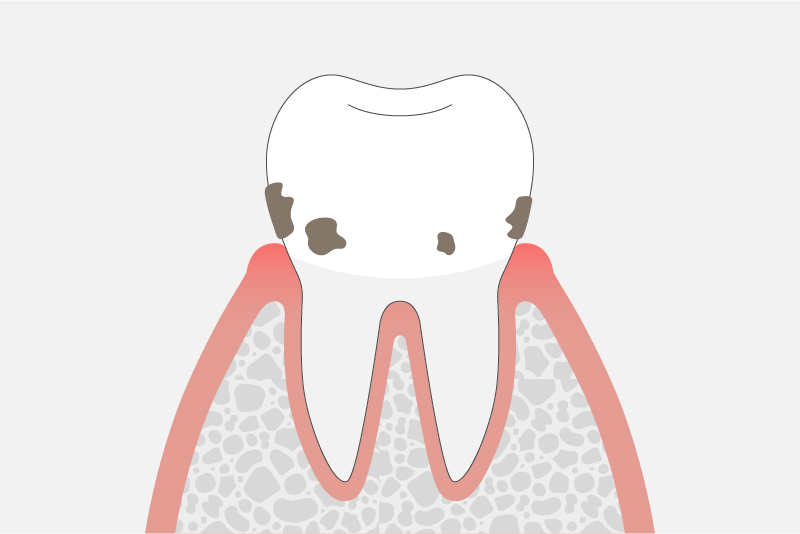

軽度歯周炎

(歯周ポケットの深さ3〜4mm)

歯を支えている骨(歯槽骨)が溶け出した状態です。

歯磨きの時に出血したり、歯がうずく、歯茎が腫れぼったく感じるなどの症状があらわれます。しかし一般的な初期段階では、まだ無症状なことが多く注意が必要です。